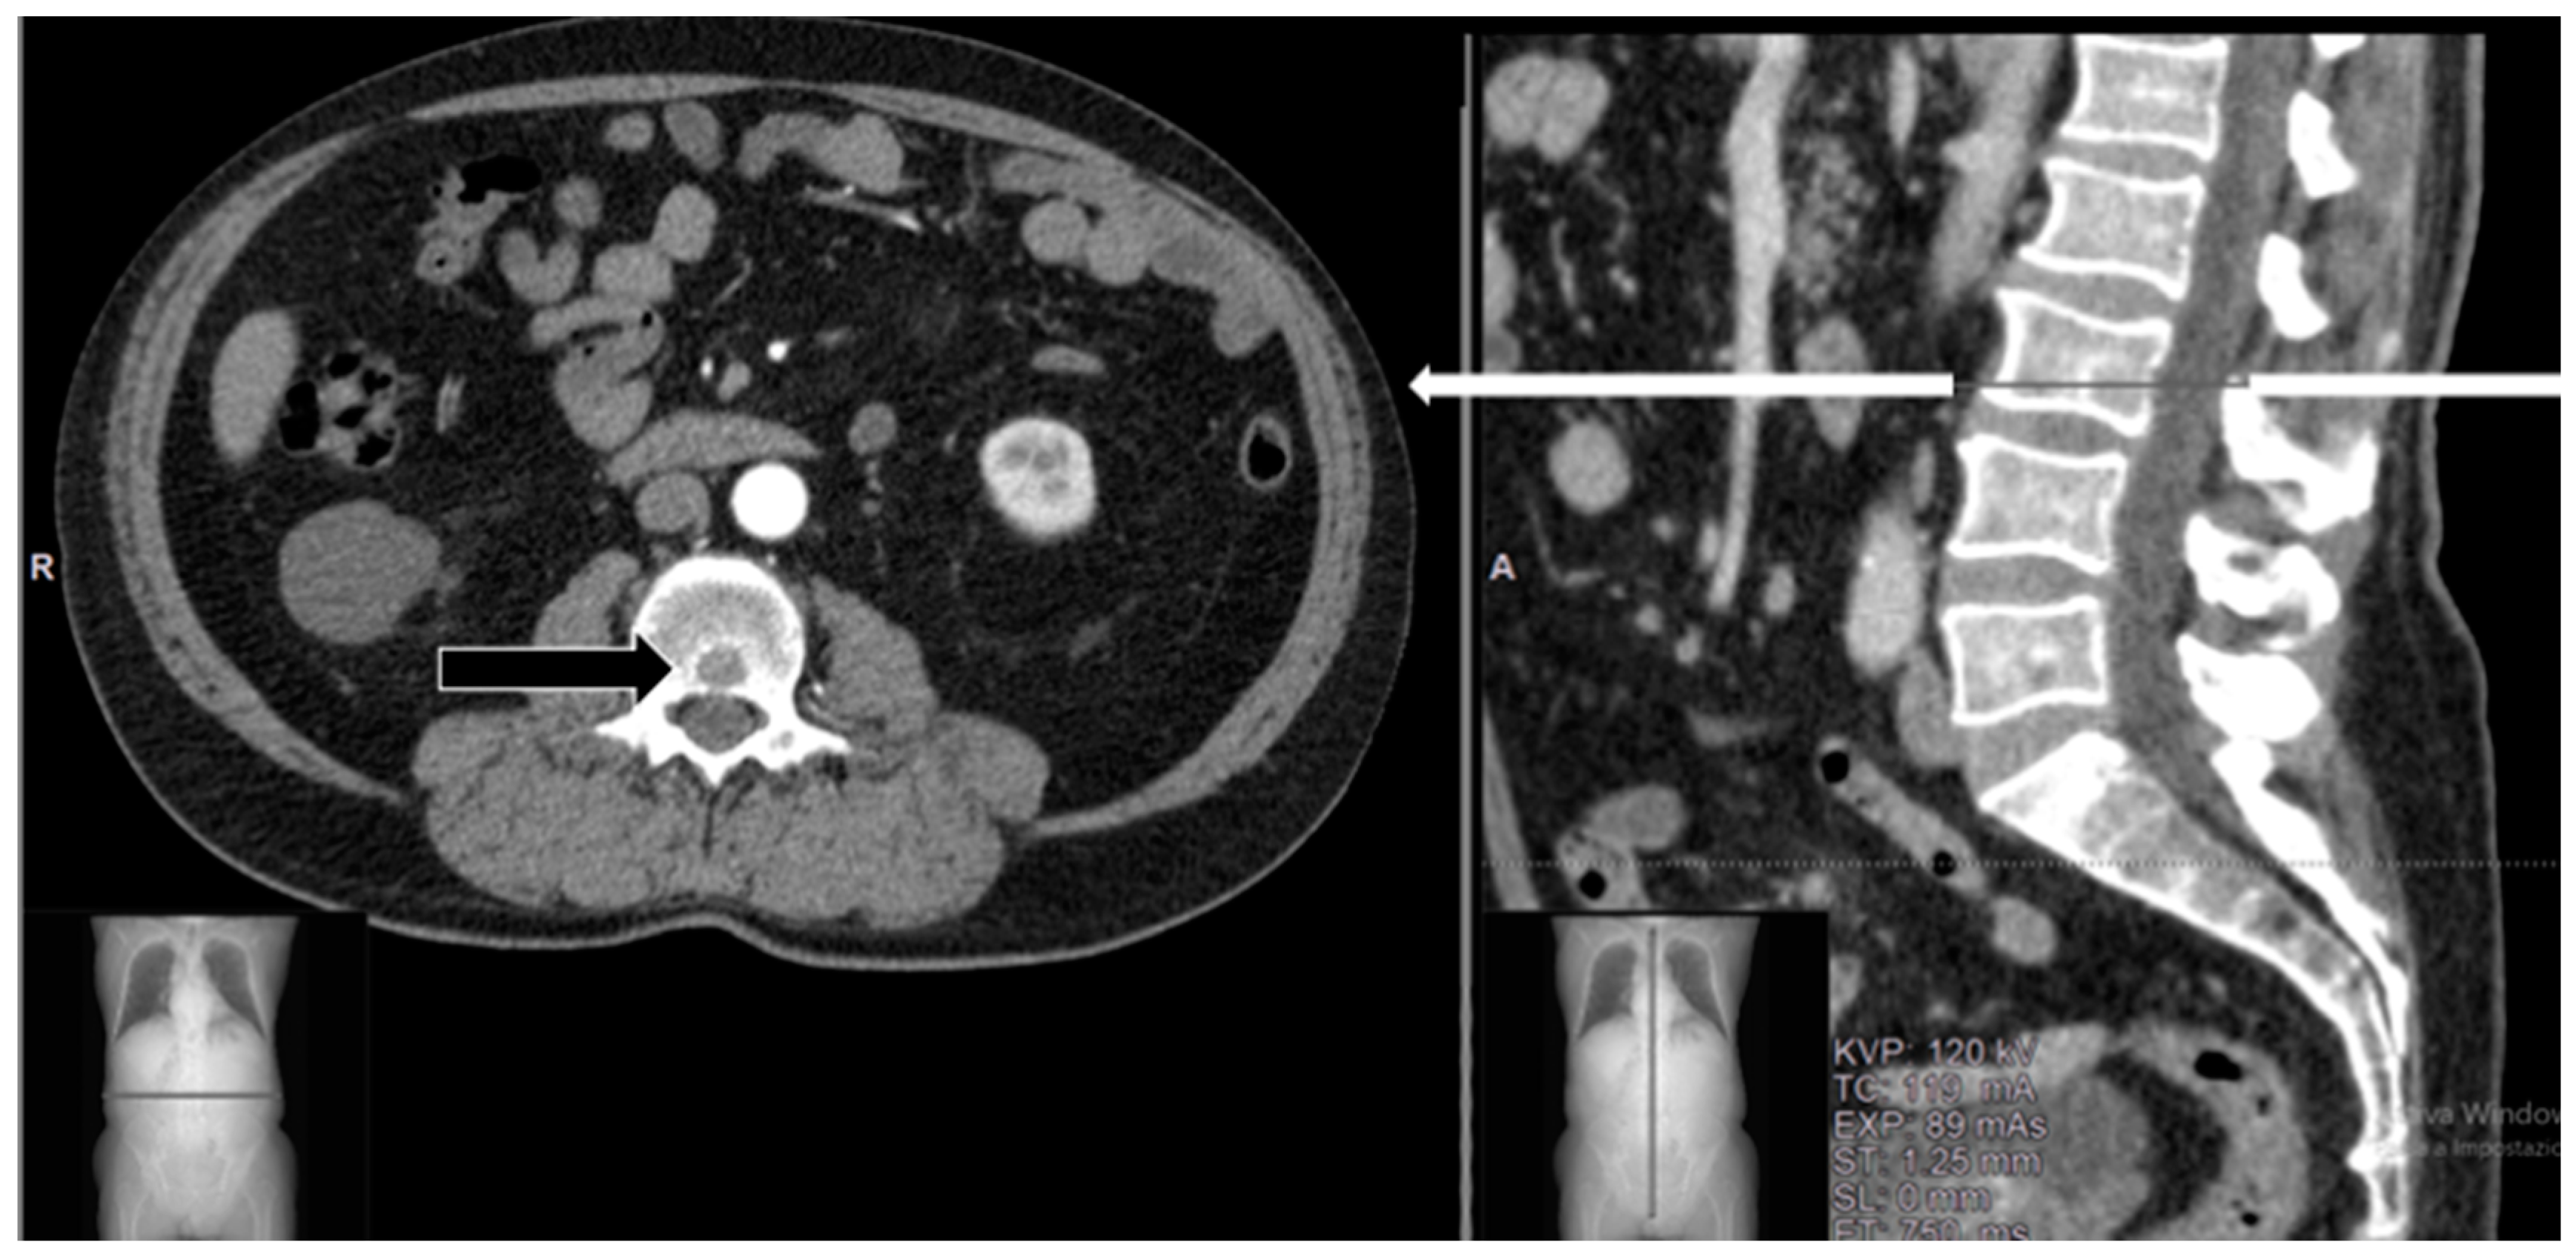

A 75-year-old female Caucasian patient with no history of oncologic disease presented with swelling on the anterior surface of the left leg. Imaging studies revealed a soft tissue suprafascial mass diagnosed as high-grade myxofibrosarcoma (G3 at FNCLCC classification) upon histopathologic evaluation of percutaneous tru-cut biopsy. Subsequently, the patient underwent surgical excision and soft-tissue reconstruction with a myocutaneous flap and cutaneous Thiersch graft. Local radiotherapy was completed with a dosage of 36 Gy within 6 months postoperatively. Six months after the completion of radiotherapy, the patient presented with suspected micronodularity in both lungs and a small lytic lesion in the L3 vertebra (Figure 2), not associated with low back pain (VAS 1).

Figure 2.

Case 1. A 75-year-old female with small lytic metastasis from high-grade myxofibrosarcoma in the L3 vertebra. The lesion was confined to the vertebral body (black arrow) without the involvement of the posterior vertebral wall. White arrow in sagittal view corresponds to the axial level.

A decision was made to conduct a short follow-up re-evaluation, which was agreed upon by the patient. Three months later, a new CT scan revealed that the lesion in the L3 vertebra had increased in volume (Figure 3a,b), and MR imaging showed partial compression of the medullary canal (Figure 3c,d). FDG-PET/CT was performed, showing increased uptake (SUV 12) (Figure 3e). The patient reported a significant worsening of pain, with pain radiating to the left thigh, but there were no ongoing peripheral neurological deficits (ASIA scale E).

Figure 3.

Case 1 at 3 months of follow-up: (a) Sagittal and (b) corresponding axial CT scans show a lytic lesion in the L3 vertebra with posterior erosion of the cortex, involving the spinal canal. (c) Sagittal T1-weighted MR imaging with contrast medium shows a homogeneous lesion at the L3 level with mixed hyperintense signal, whereas in (d) sagittal T2-weighted MRI, the lesion appears hypointense. (e) FDG-PET/CT on axial view shows the intense focal area of 18-FDG activity in the L3 vertebral body.